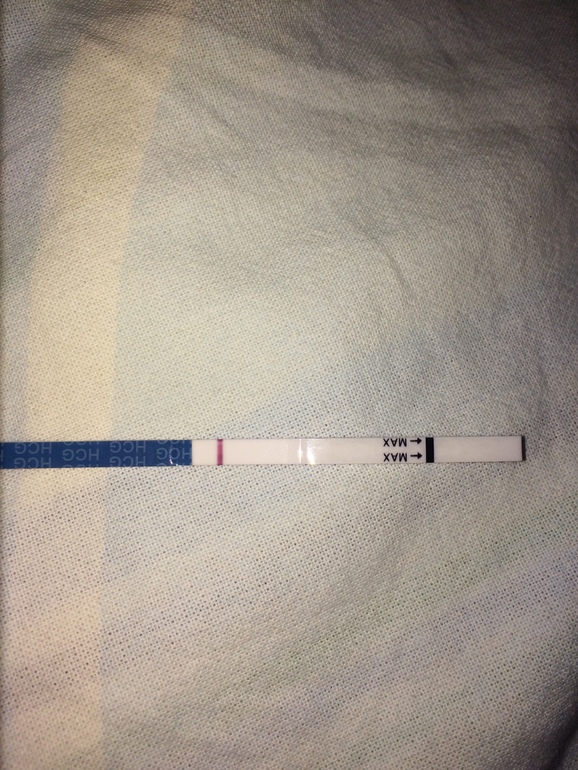

Девочки, сегодня 20 д. ц. , цикл 25-27 дней, первый цикл на дюфастоне с 10 по 25 д. ц. Честно говоря особо не надеялась, да и рано наверно ещё, но что то вдруг подтолкнуло и я зашла в аптеку)).

Девочки, сегодня 20 д. ц. , цикл 25-27 дней, первый цикл на дюфастоне с 10 по 25 д. ц. Честно говоря особо не надеялась, да и рано наверно ещё, но что то вдруг подтолкнуло и я зашла в аптеку)).

Я вроде видела, когда сырая была, но подсохла и исчезла, через день повторю, особо конечно не надеюсь, начиталась про дюф что до овули нельзя, но решила следовать рекомендации врача, в след цикл буду отслеживать и бт мерить, до месячных ещё неделя, может быть ещё рано тесты мочить, да и живот тянет как перед ними..

И главное её было видно сразу как намокла, когда высохла не видно.

Пока пусто. Я раньше тоже разглядывала полосочки, но если Б есть - полоску будет видно сразу.

Пусто.Рано ещё,ждите дальше и пусть будут //

Когда фото приближаю контуры видать, реагент?

Побаловалась ещё с фоторедактором, там вообще видно и присматриваться не надо! Хоть бы оно!

О, такой же брат-близнец сегодня был. Не знаю, как расценивать) И тоже 20ДЦ

Она похоже